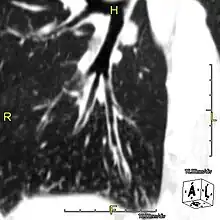

Around 80% of people with primary ciliary dyskinesia experience respiratory problems beginning within a day of birth. Many have a collapsed lobe of the lung and blood oxygen low enough to require treatment with supplemental oxygen.[1] Within the first few months of life, most develop a chronic mucus-producing cough and runny nose.[1] The main consequence of impaired ciliary function is reduced or absent mucus clearance from the lungs, and susceptibility to chronic recurrent respiratory infections, including sinusitis, bronchitis, pneumonia, and otitis media. Progressive damage to the respiratory system is common, including progressive bronchiectasis beginning in early childhood, and sinus disease (sometimes becoming severe in adults). However, diagnosis is often missed early in life despite the characteristic signs and symptoms.[2] In males, immotility of sperm can lead to infertility, although conception remains possible through the use of in vitro fertilization, there also are reported cases where sperm were able to move.[8] Trials have also shown that there is a marked reduction in fertility in females with Kartagener's syndrome due to dysfunction of the oviductal cilia.[9]

When accompanied by the combination of situs inversus (reversal of the internal organs), chronic sinusitis, and bronchiectasis, it is known as Kartagener syndrome[3] (only 50% of primary ciliary dyskinesia cases include situs inversus).[11]